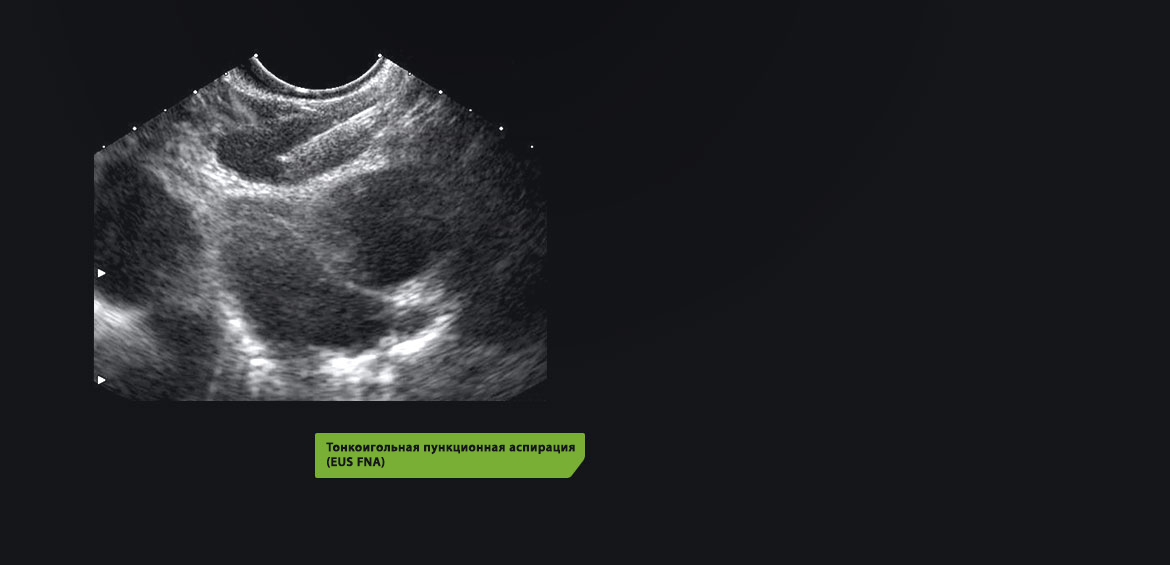

Благодаря высокому разрешению цифровой ультразвуковой системы High-Resolution EUS стало возможным более точное выявление и определение стадии заболевания при исследовании медиастинальных лимфатических узлов с помощью тонкоигольной пункционной биопсии/аспирации (EUS FNB/FNA). Возможность использования ультразвуковой эндоскопии пищевода и эндобронхиального ультразвукового исследования помогает врачу максимально точно диагностировать степень заболевания.

• Безопасное позиционирование иглы для тонкоигольной пункционной биопсии/аспирации (FNВ/FNA) под контролем ультразвука.

Ультразвуковые гастроскопы Pentax оснащены радиальными или продольными датчиками Hitachi. Модель с радиальным ультразвуковым датчиком и охватом 360° предоставляет эндоскописту новый уровень точности диагностических исследований всех необходимых участков. Модели гастроскопов с продольным датчиком обеспечивают проведение максимально эффективной тонкоигольной биопсии/аспирации.